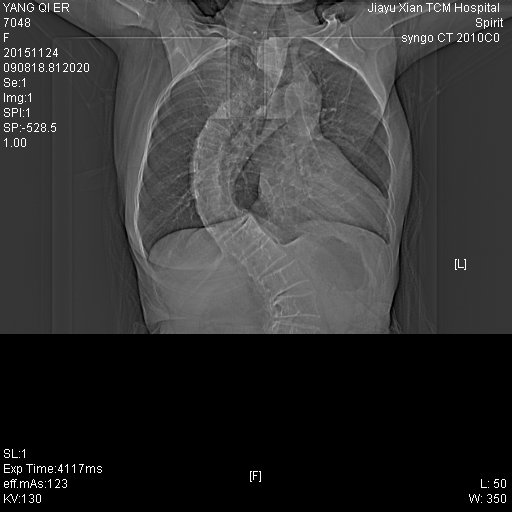

CT51355:女.69岁,胃部不适

自诉吃东西有点梗阻,请各位老师看看

1、胃间质瘤可能。

2、脊柱侧弯畸形。

胃窦占位,建议胃镜

胃壁增厚,建议结合胃镜检查,肝右叶小圆形低密度影,小囊肿可能。

1.胸椎向右侧侧弯, 胸廓畸形

2.符号慢性支气管炎

3.右侧胸膜肥厚